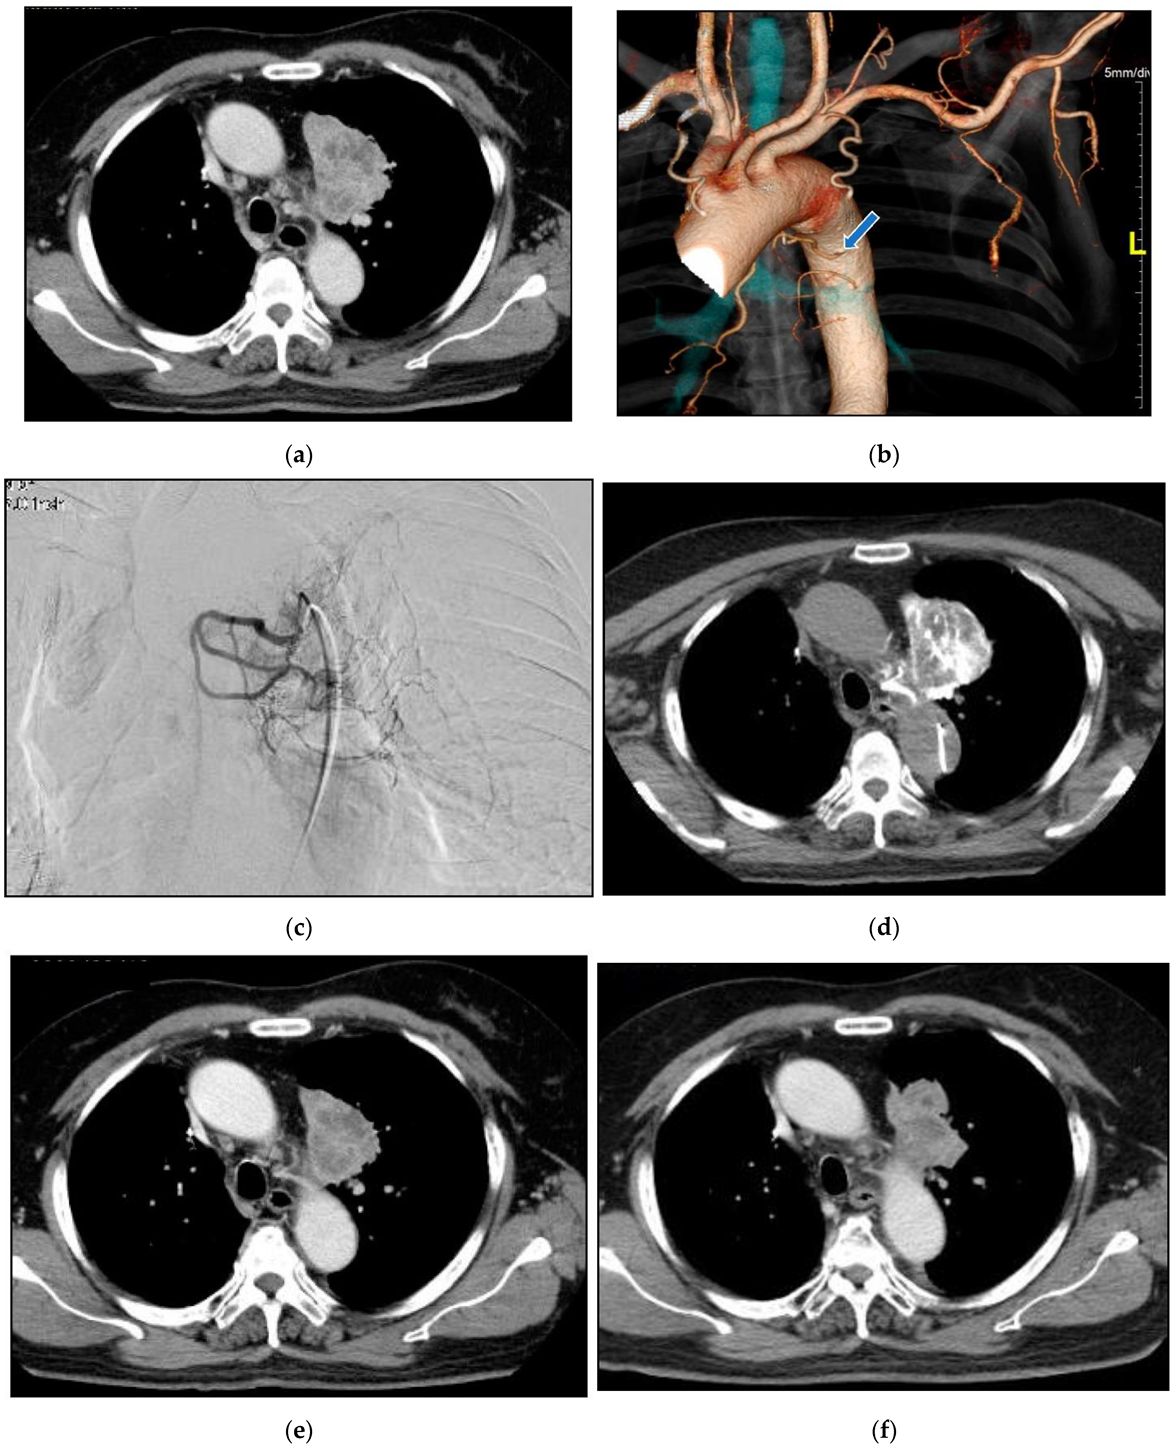

Case 2: A 75-year-old woman consulted our clinic complaining of severe cough (Figure 11). A Tumor located in the proximal part of the right upper lobe caused atelectasis of the right upper lobe. She had not undergone systemic chemotherapy due to her age and concomitant bronchiectasis. The first treatment through the bronchial arteries was carried out by infusing docetaxel; 20 mg, cisplatin; 20 mg, bevacizumab; 100 mg with embolization by 1.0 mg of fluorouracil loaded HepaSphere (50–100 micron). In total, 6 sessions of treatment have been repeated to maintain better QOL. The patient died from obstructive pneumonia 29 months after the initial treatments.

Complete disappearance of the target lesion was found and intrapulmonary metastases in the right lung were newly detected.

Figure 11. A 75-year-old female with right lung cancer. (a): A contrast-enhanced CT. The tumor (circle) around the right upper bronchus caused atelectasis of the right upper lobe. (b): A volume rendering 3D image demonstrates the common trunk (arrow) of the bronchial and intercostal artery. The right bronchial artery (arrowhead) distributes along the right upper bronchus. (c): Selective DSA of the right main bronchial artery. Abnormally dilated vessels were demonstrated around the right upper bronchus. (d): Angio-CT of the right bronchial artery. The tumor causing atelectasis of the right upper lobe was enhanced. (e): A contrast-enhanced CT in a month after the initial therapy. Shrinkage of the tumor was found and atelectasis was improved. (f): A contrast-enhanced CT in 20 months after the initial therapy. Six sessions of treatment were repeated in the same manner.